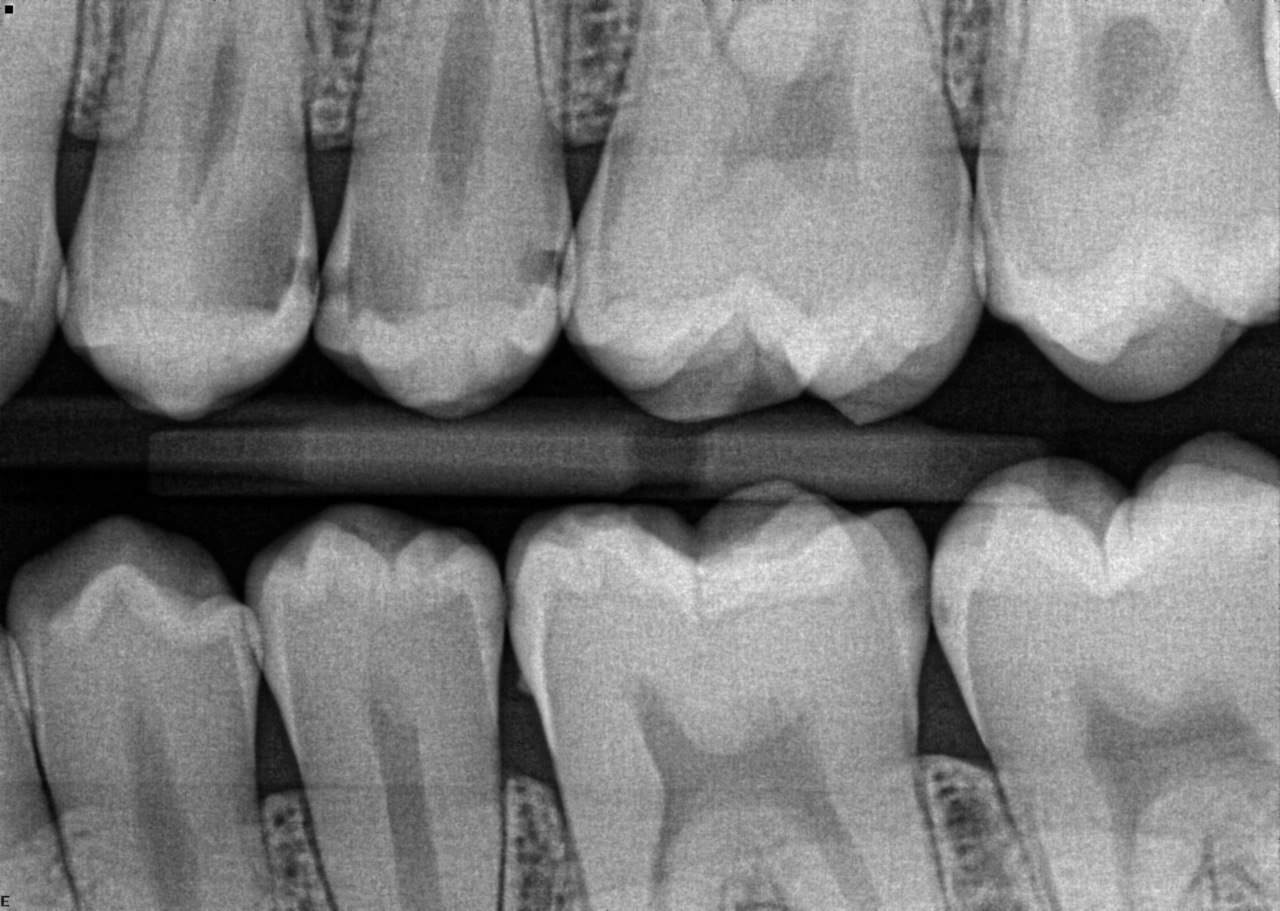

Question 1: What is the condition of the mesial surface of the tooth # 2.6?

Question 2. What is the condition of the mesial of the tooth # 2.7?

Question 3. What is the condition of the distal surface of the tooth # 2.7 and mesial surface of the tooth # 2.8 respectively?

Question 4: what is the condition of the distal of the tooth # 4.1 and mesial of the tooth #3.1 respectively?